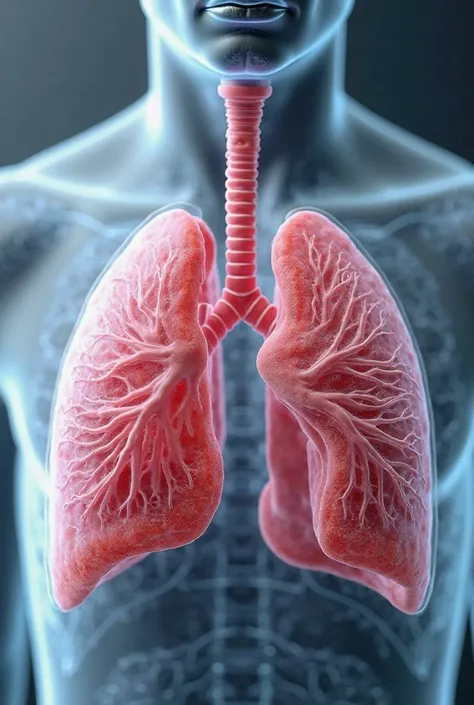

Make a folder about bacterial pneumonia

Make a folder about bacterial pneumonia

Make a folder about bacterial pneumonia